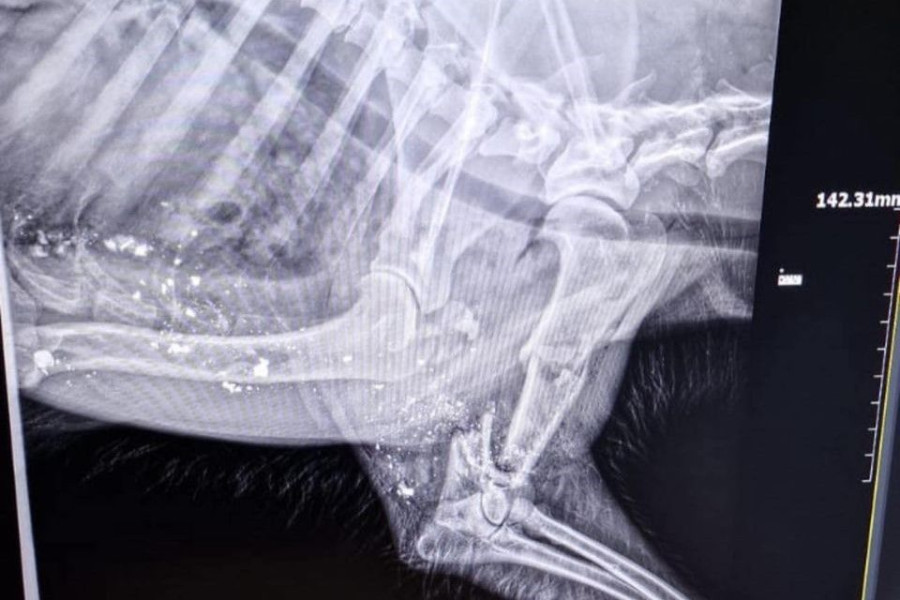

Jeden wrócił z głęboką raną postrzałową (stan psa ciężki).

Właściciele psa udali się do weterynarza w sąsiednim powiecie, gdzie usłyszeli, że kula roztrzaskała zwierzęciu łopatkę. I że ktoś, kto strzelał, musiał mierzyć prosto w serce.

Piesek, który dziś lub jutro miał mieć operację, mimo opieki umarł w męczarniach. Niestety, nie udało się go uratować.